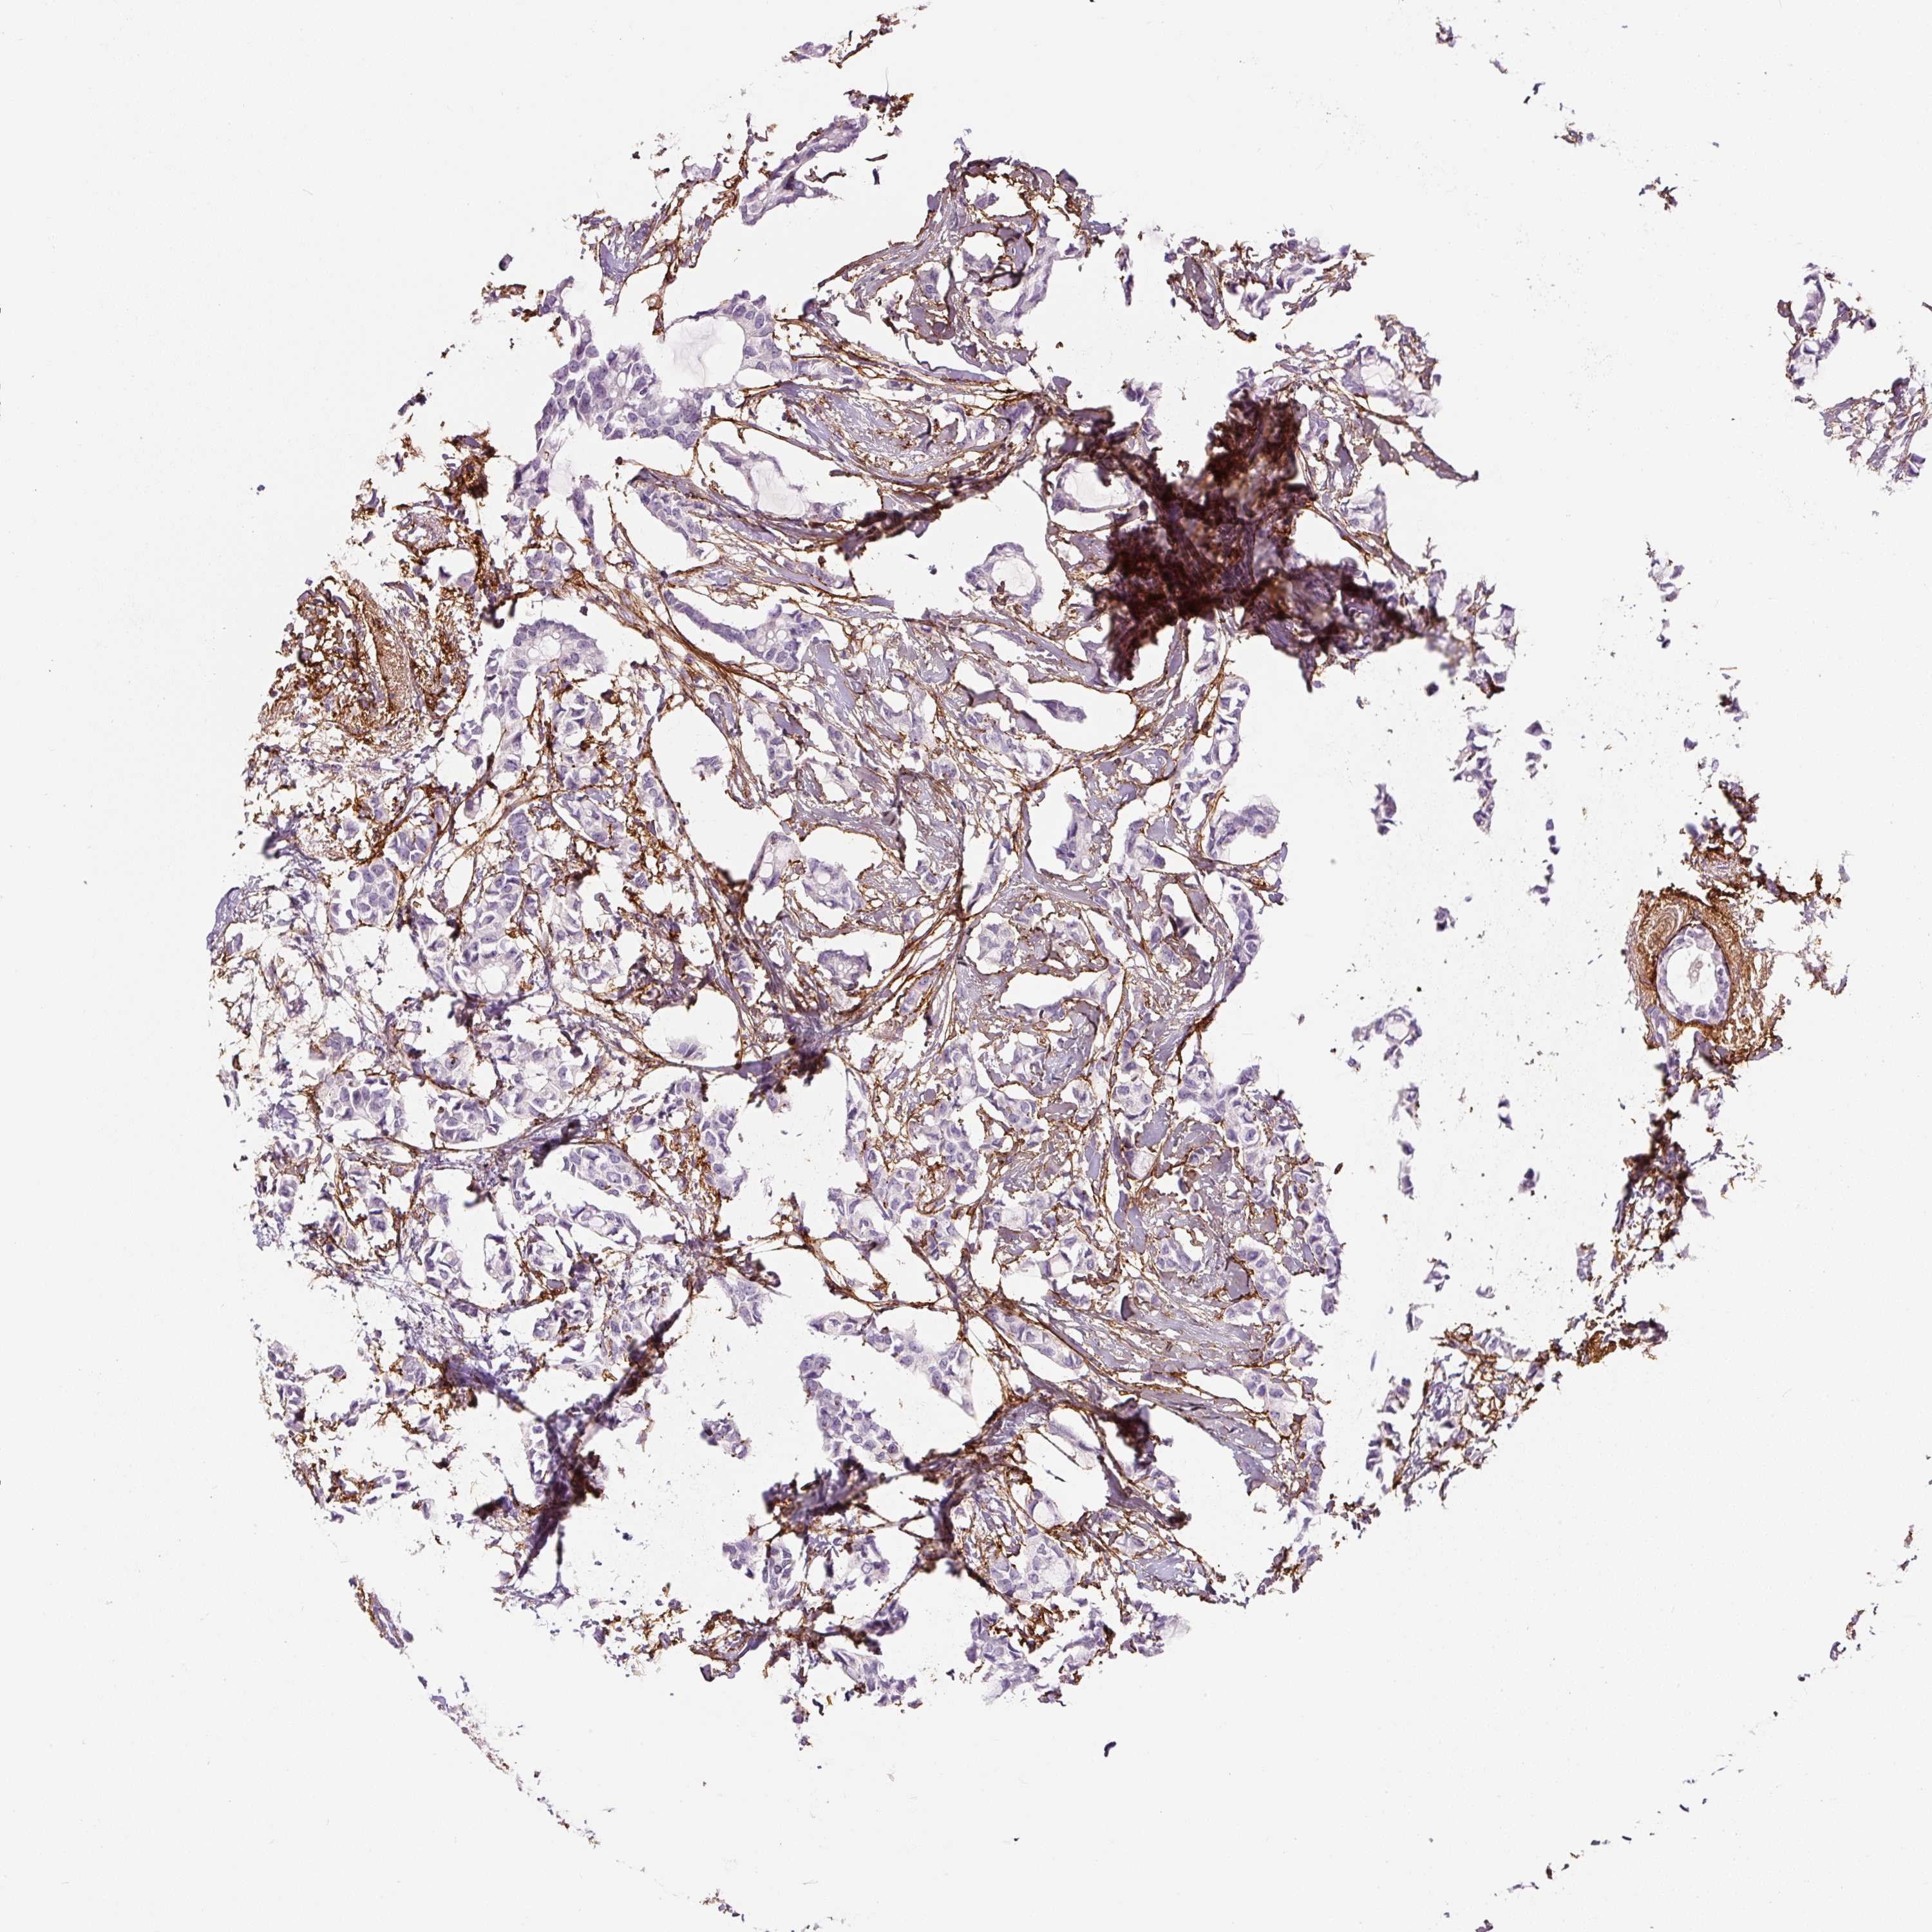

CANCER BREAST CANCER Show tissue menu

BRCA TCGA BRCA VALIDATION PROTEIN EXPRESSION

Breast cancer

Human cancer

Breast invasive carcinoma